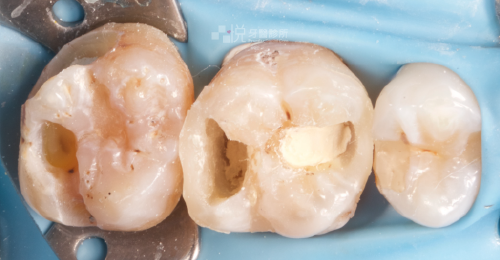

活髓保存術是牙齒因深度蛀牙、外傷等原因,導致內部牙髓組織快暴露與已暴露在外界時所做的治療,藉由良好的生醫材料,創造出保護神經的屏障,讓牙髓神經恢復健康,刺激牙本質的生成。

活髓保存術的主要生醫材料是水矽酸鈣基底材料( hydraulic calcium silicate-based cements ),其主要成分是矽酸二鈣或三鈣。

材料有高生物相容性,可同時保護牙髓組織並促使牙髓組織生成保護屏障,且內含的礦化材料可以和牙本質結合促進牙本質再礦化。